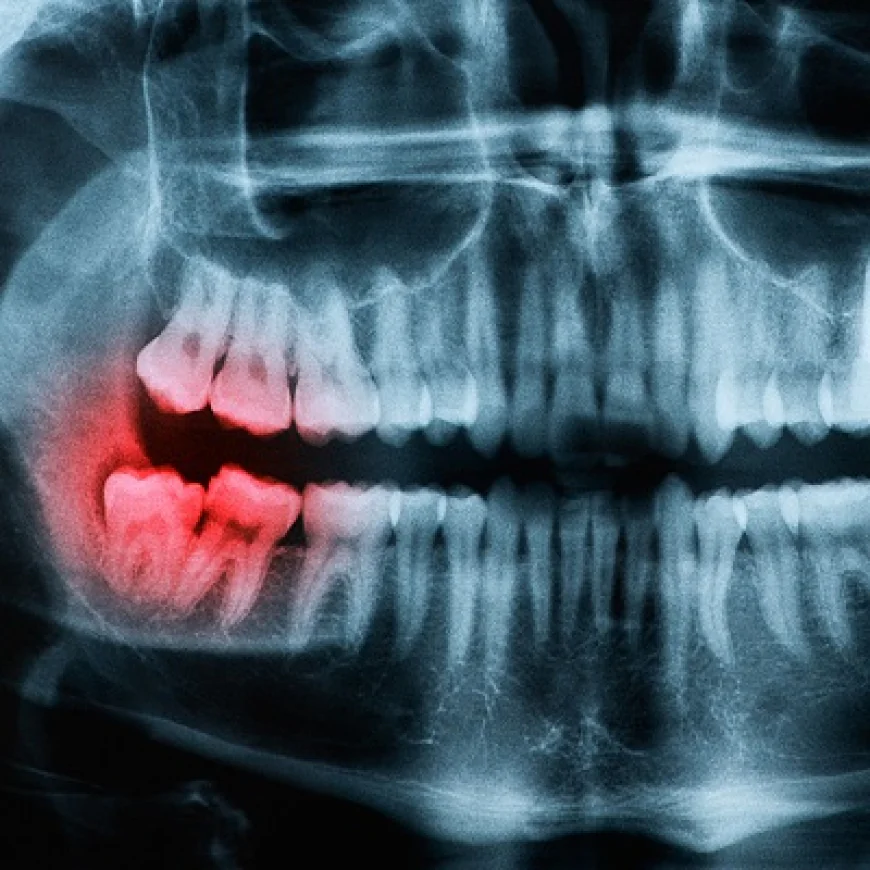

A dental panoramic X-ray—also known as an orthopantomogram (OPG)—is a specialized imaging method that captures the entire mouth, including the upper and lower jaws, teeth, temporomandibular joints (TMJs), and surrounding bone structures, in a single wide-angle image.

Unlike small intraoral X-rays that focus on one area at a time, panoramic imaging offers a broad perspective, which is especially valuable for spotting issues that might not be visible in a standard dental examination.

2. Evaluating Wisdom Teeth:

Wisdom teeth, also known as third molars, often erupt improperly due to lack of space, leading to impaction, pain, or infection. A panoramic X-ray clearly shows:

The exact position of wisdom teeth

Their angle of eruption

Their proximity to nerves and sinuses

This information helps dentists determine whether extraction is necessary and how to plan it with minimal risk.